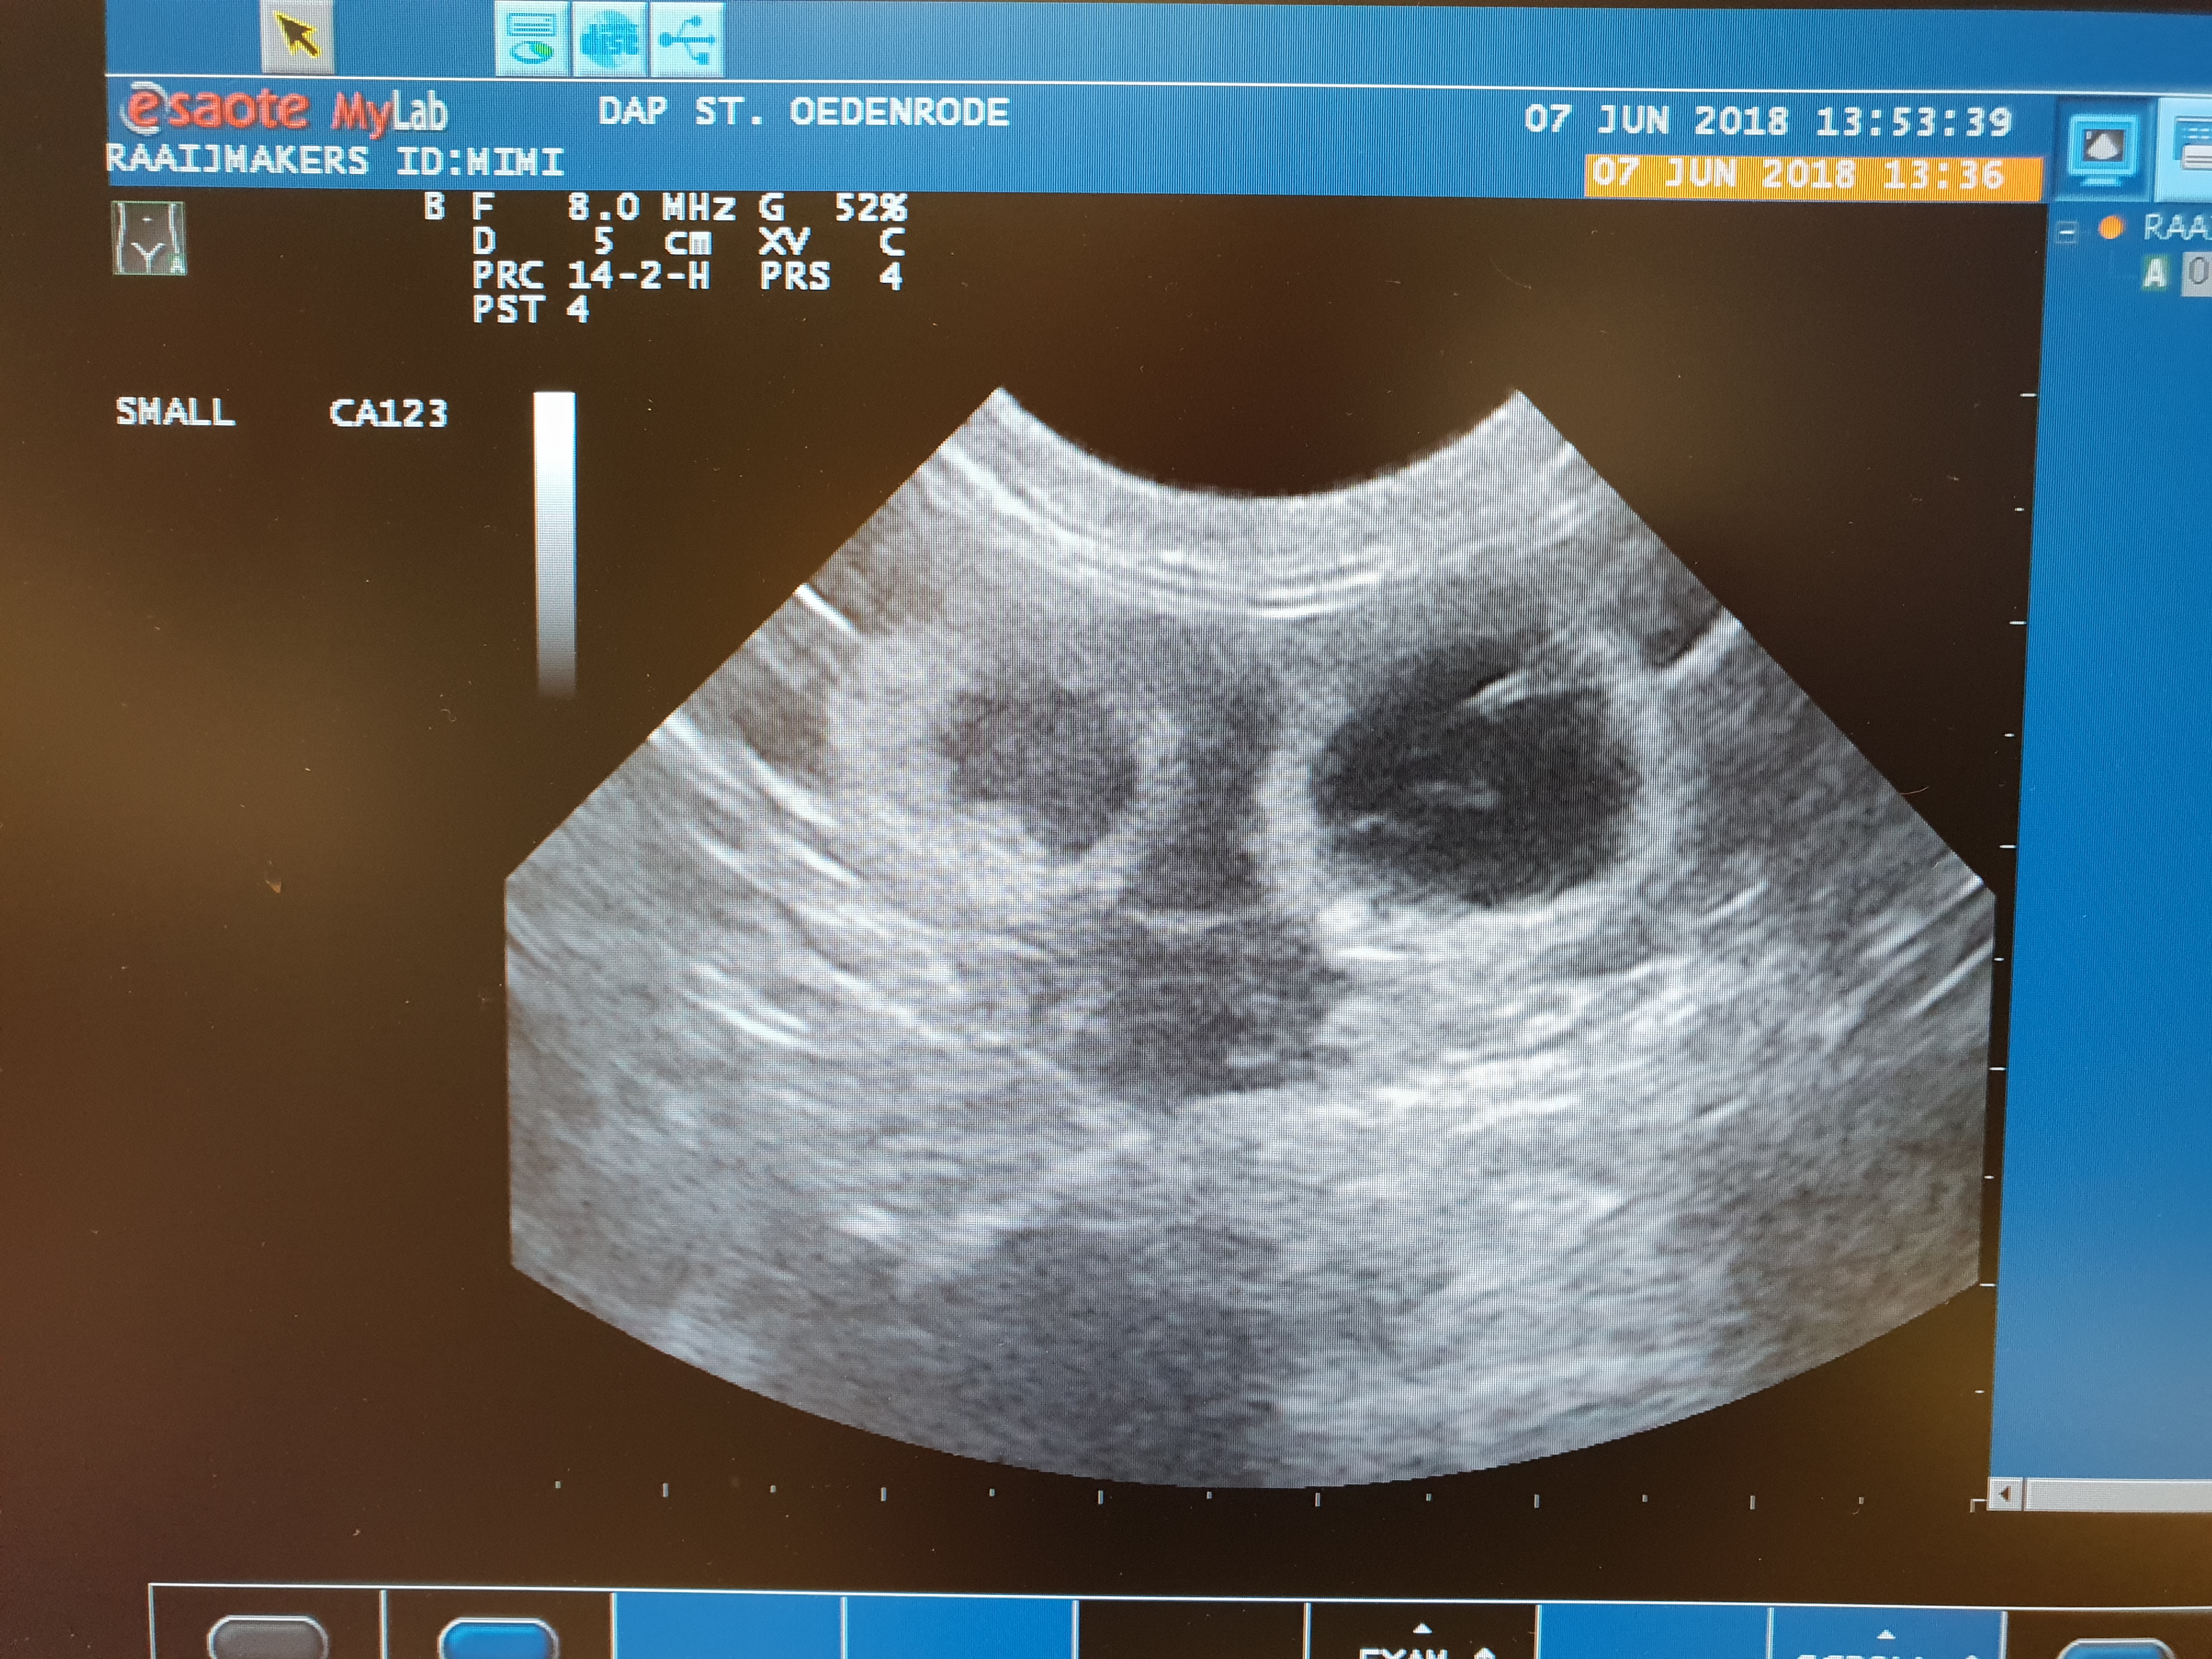

Toen we aankondigden dat Aislinn zwanger was, zagen we het gezichtje van Mili al: “Ik wil ook kleintjes.” en een paar dagen later liet ze blijken dat ze het serieus meende, dus hebben we haar weer naar Bikimi’s Salvador Dali gebracht voor een gezellig samenzijn. En dat dit samenzijn succesvol is geweest, heeft de echo uitgewezen. Naar verwachting en hopelijk zullen twee kittens in de tweede helft van juli het levenslicht gaan zien.